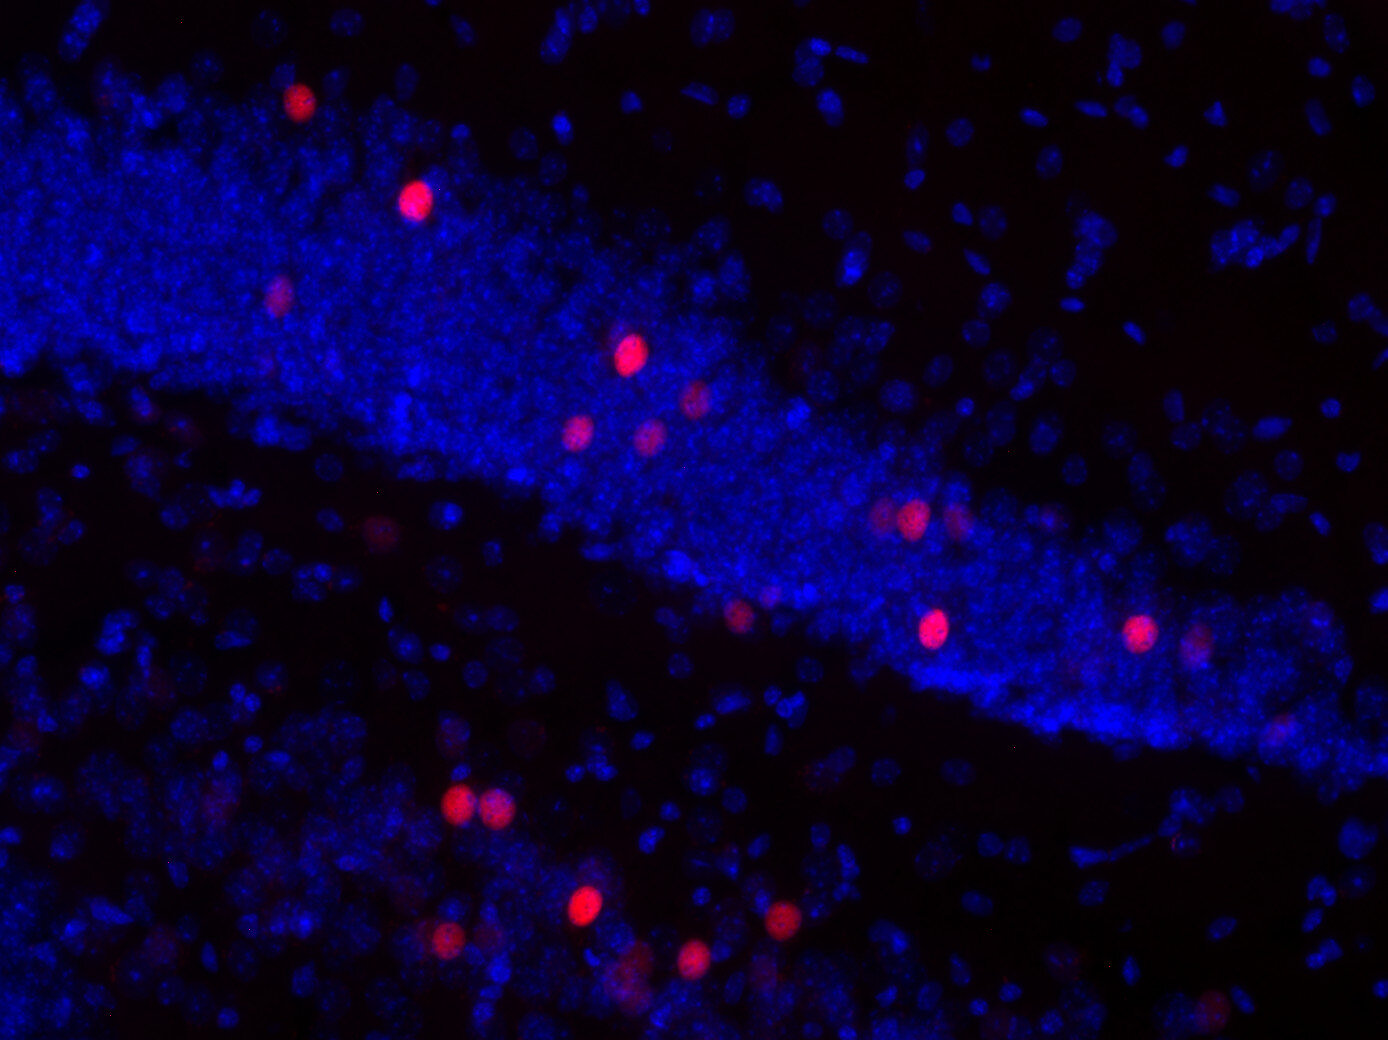

70386-2/asset/392a6bc4-3dab-4838-82e2-d7134cbd4082/main.assets/gr2_lrg.jpg)